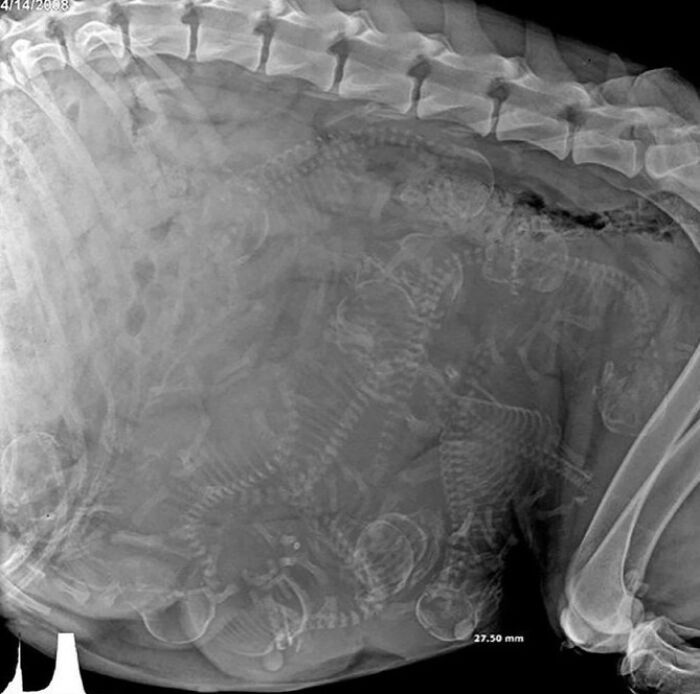

#1 Röntgenový snímok, na ktorom vidíme tehotnú sučku